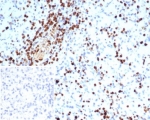

IHC staining of FFPE human spleen tissue with S100A4 antibody (clone S100A4/7097). Inset: PBS used in place of primary Ab (secondary Ab negative control). HIER: boil tissue sections in pH 9 10mM Tris with 1mM EDTA for 20 min and allow to cool before testing.